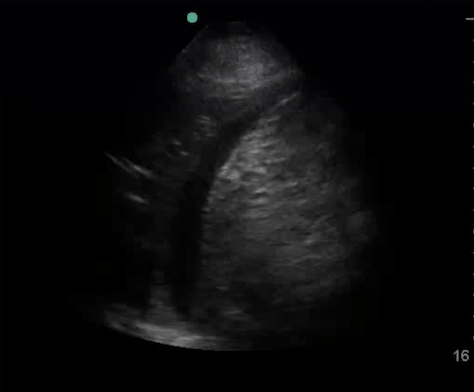

• Focused cardiac assessment

• Focused cardiac assessment for systolic function and pericardial effusion